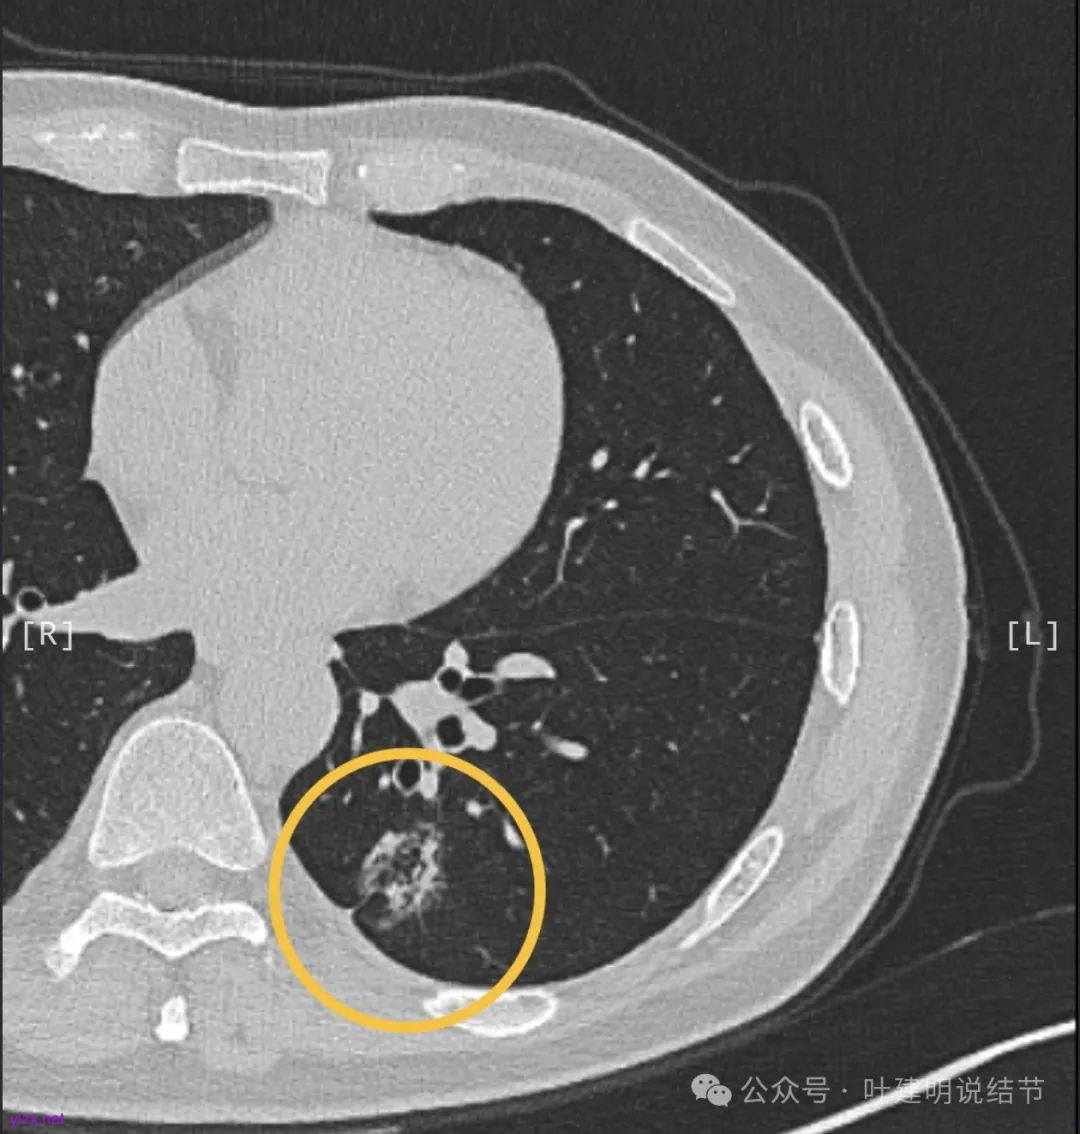

第1次问诊的时候,我就说这个病灶考虑是浸润性腺癌,但是由于合并存在局灶支气管扩张,所以不能100%确认。但是建议他年后找时间早点手术切了。

第3次问诊的时候,患者告诉我已经在当地一个很大的医院(全国非常著名)做了手术,术中病理报的是肺泡上皮不典型增生,倾向腺癌。我不知道这是个怎样的诊断,到底是不典型增生还是腺癌。但是我认为术后病理是会升级的,由于磨玻璃成分为主,实性成分占比比较少,所以我当时考虑即使升级也是高分化浸润性腺癌可能性大。

最近反馈给我的信息,常规病理果然升级了,但是有所意外的是,高危亚型占5%。贴壁亚型只有15%。当然这也符合之前总结的,囊腔型病灶如果是浸润性癌,容易含有低分化成分。